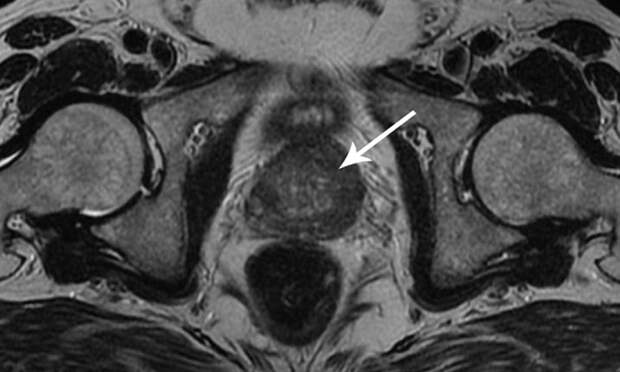

МРТ при подозрении на опухоль предстательной железы

Используется динамическое контрастирование для точного определения областей для биопсии и планирования лечения. Диффузионная визуализация, улучшают точность диагностики.